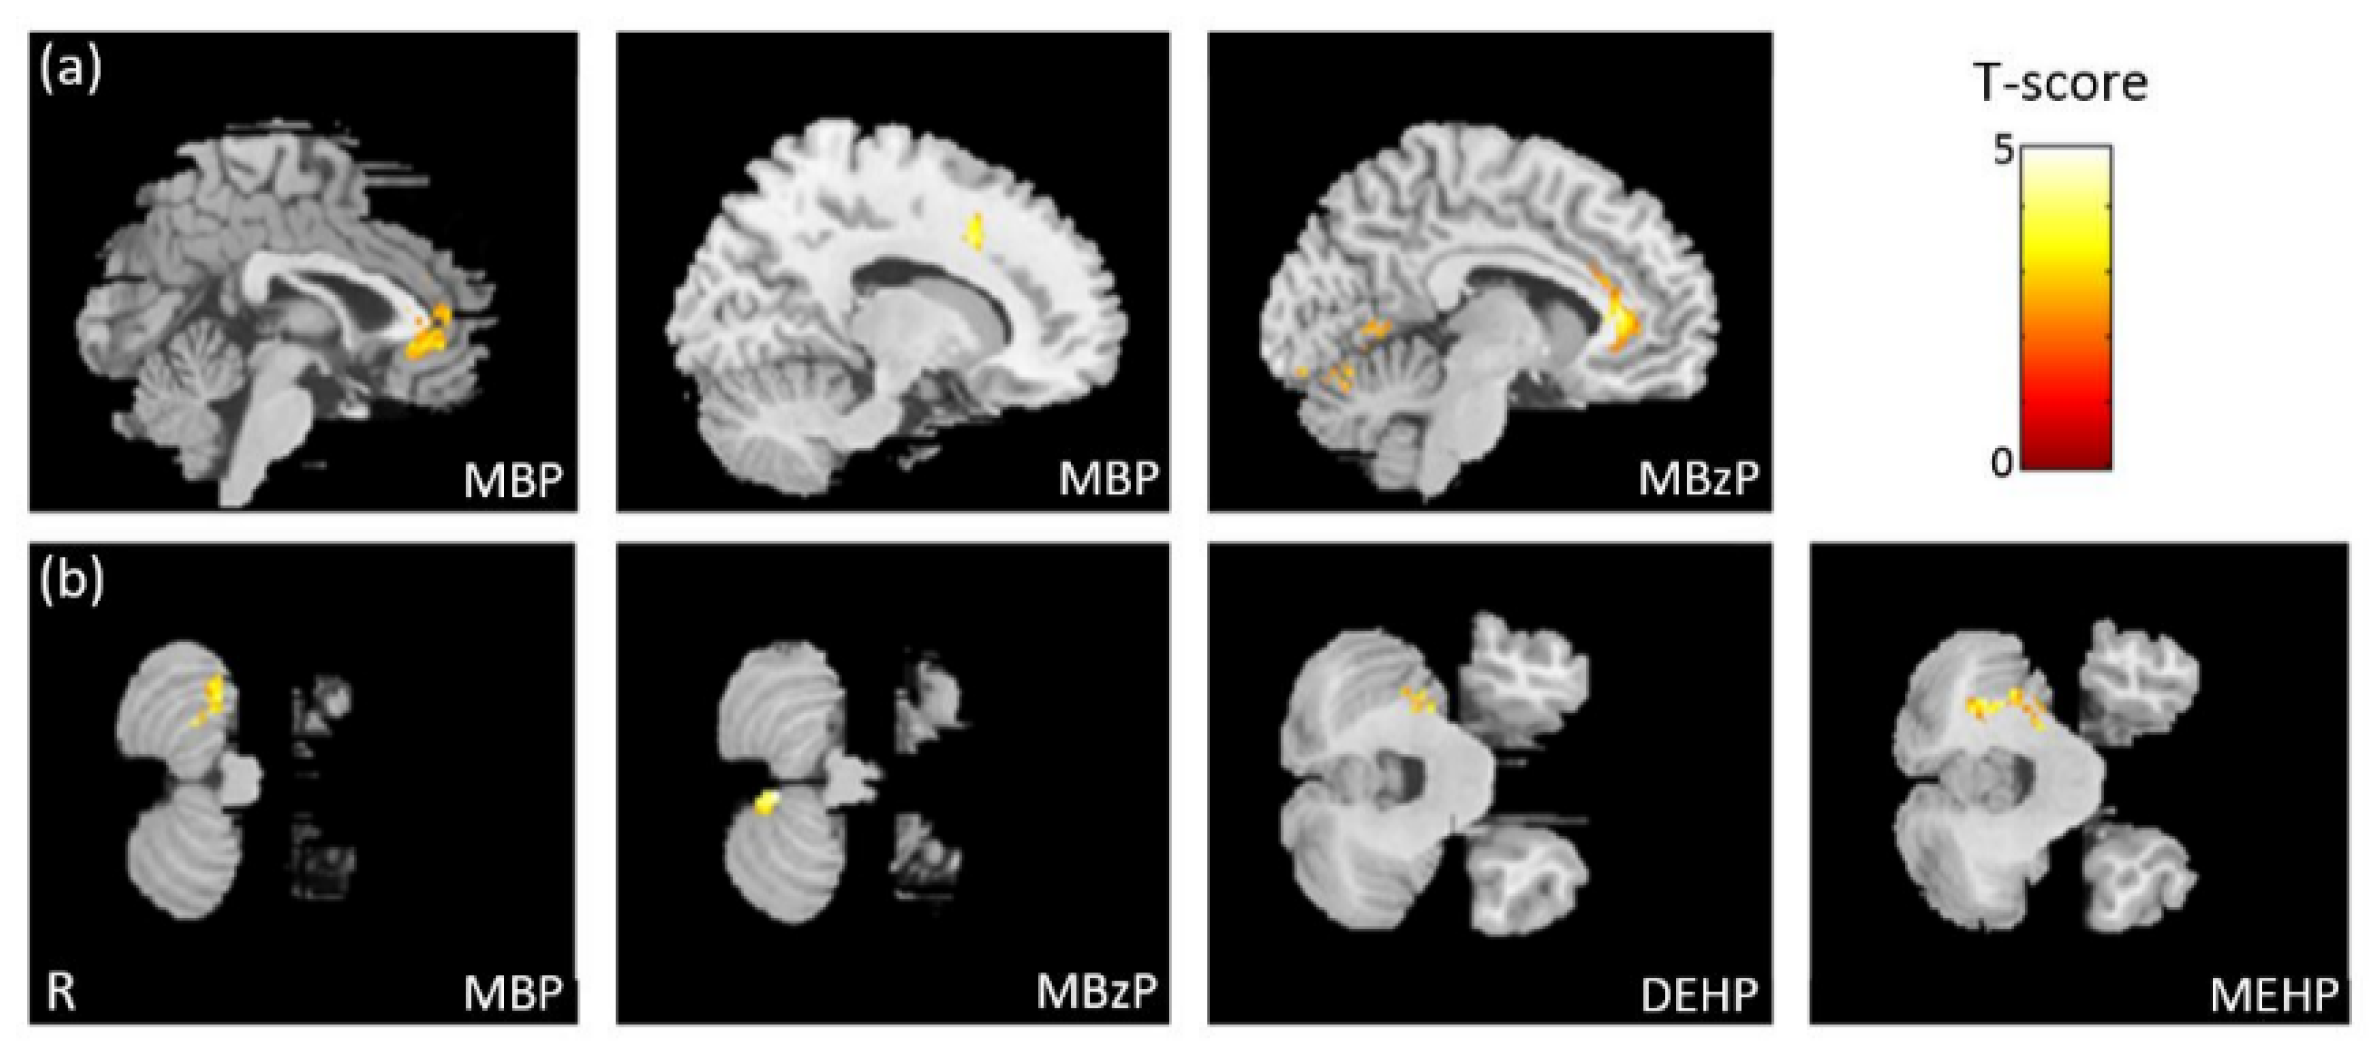

3.2. The Association between Phthalate Esters and VBM

3.5. The Association between Phthalate Esters and GQI

4.1. Brain Volume and White Matter Structure Associated with Phthalate Esters